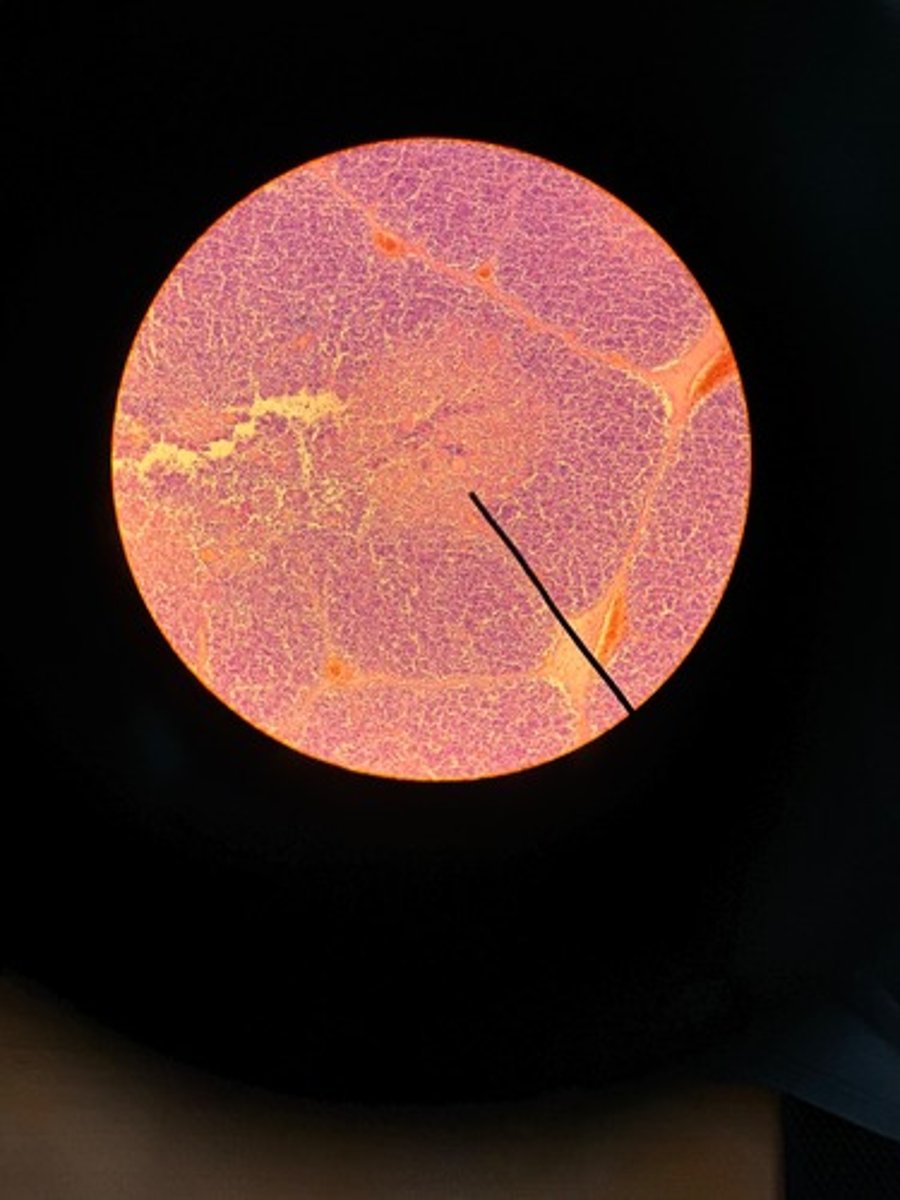

Adrenal gland HE

Adrenal gland HE

Adrenal gland HE

Adrenal gland HE

Adrenal gland

Adrenal gland HE